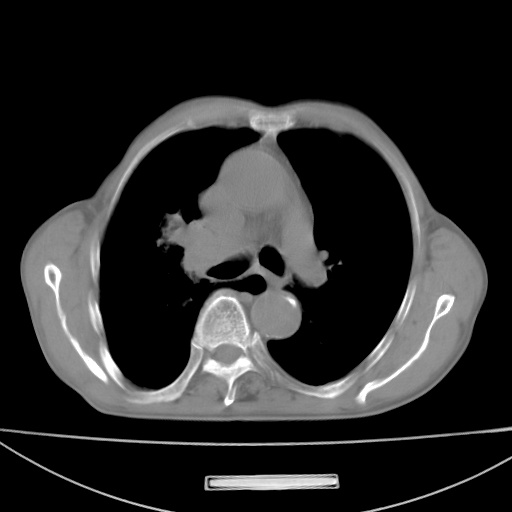

标题: CT13796:请会诊右上费病变!

患者男80岁,反复咳嗽多年,咳喘伴咯血1月

右上肺周围型肺癌伴肺门淋巴结转移.右上肺继发型肺结核.

右上肺周围型肺癌伴肺门淋巴结转移

右肺上叶占位性病变,考虑周围型肺癌,肺门淋巴结转移。要是能提供更多的临床资料就好了,以供鉴别诊断。

右肺上叶占位性病变,考虑周围型肺癌,肺门淋巴结转移。

右上肺周围型肺癌伴肺门、纵膈淋巴结转移

考虑为:右肺上叶肺癌伴阻塞性肺炎、右肺门及纵膈淋巴结转移。